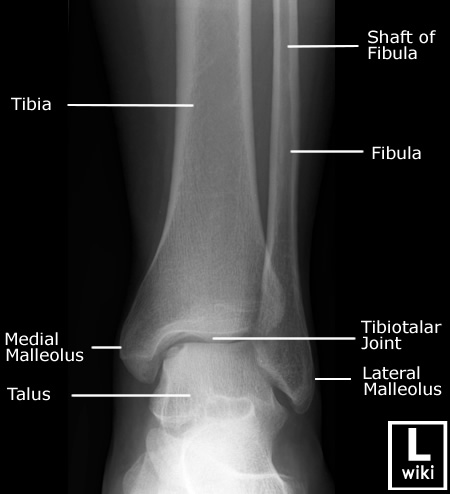

| [Anatomy] Ankle(발목) (0) | 2024.01.25 |